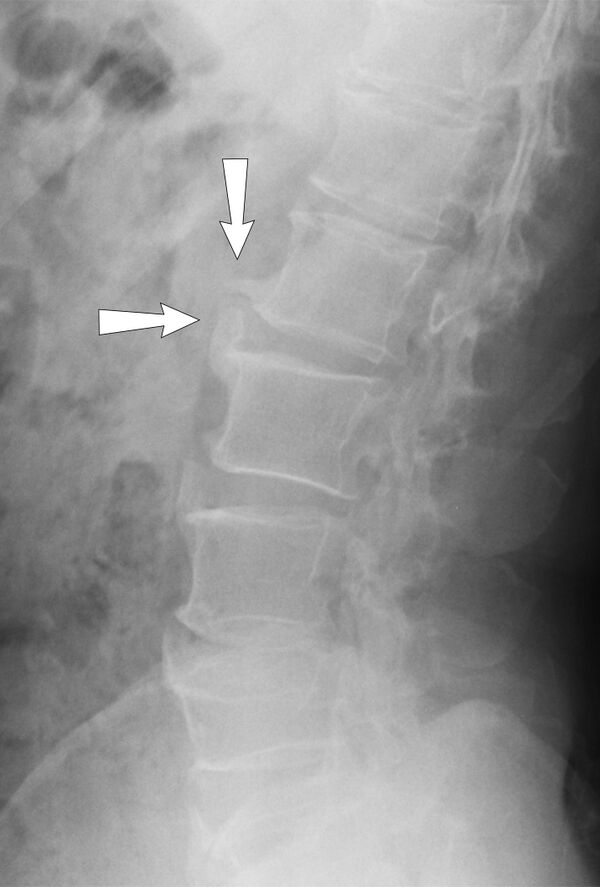

При спондилёзе костная ткань суставов разрастается, образуются остеофиты, то есть дополнительная костная ткань (по мере нарастания костный вырост распространяется к соседнему позвонку, тогда как от соседнего позвонка образуется такой же вырост, в некоторых случаях окостенение начинается на уровне межпозвоночного диска). В особо тяжёлых случаях наступает сращение позвонков, от чего страдают сосуды, нервы и мышечная ткань, а также близлежащие органы[4].